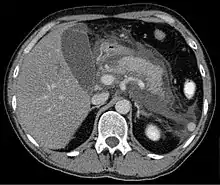

Computed tomography

Regarding the need for computed tomography, practice guidelines state:

CT is an important common initial assessment tool for acute pancreatitis. Imaging is indicated during the initial presentation if:

- the diagnosis of acute pancreatitis is uncertain

- there is abdominal distension and tenderness, fever >102 F (38,9 C), or leukocytosis

- there is a Ranson score > 3 or APACHE score > 8

- there is no improvement after 72 hours of conservative medical therapy

- there has been an acute change in status: fever, pain, or shock

CT is recommended as a delayed assessment tool in the following situations:

- acute change in status

- to determine therapeutic response after surgery or interventional radiologic procedure

- before discharge in patients with severe acute pancreatitis

Abdominal CT should not be performed before the first 12 hours of onset of symptoms as early CT (<12 hours) may result in equivocal or normal findings.

CT findings can be classified into the following categories for easy recall:

- Intrapancreatic – diffuse or segmental enlargement, edema, gas bubbles, pancreatic pseudocysts and phlegmons/abscesses (which present 4 to 6 wks after initial onset)

- Peripancreatic / extrapancreatic – irregular pancreatic outline, obliterated peripancreatic fat, retroperitoneal edema, fluid in the lessar sac, fluid in the left anterior pararenal space

- Locoregional – Gerota's fascia sign (thickening of inflamed Gerota's fascia, which becomes visible), pancreatic ascites, pleural effusion (seen on basal cuts of the pleural cavity), adynamic ileus, etc.

The principal value of CT imaging to the treating clinician is the capacity to identify devitalised areas of the pancreas which have become necrotic due to ischaemia. Pancreatic necrosis can be reliably identified by intravenous contrast-enhanced CT imaging,[20] and is of value if infection occurs and surgical or percutaneous debridement is indicated.